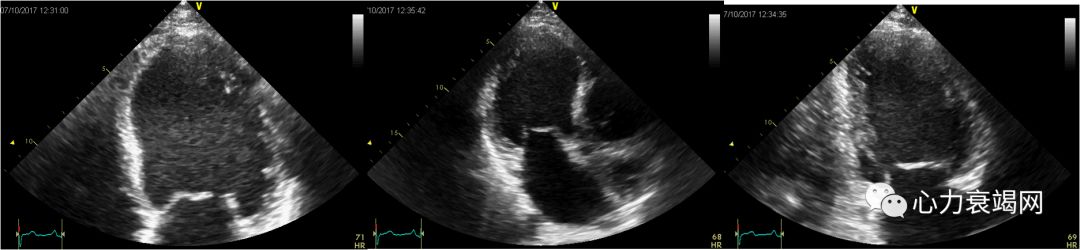

女,16岁。反复发热4年,活动后胸闷气短7月

ANA、抗Sm抗体、抗nRNP及抗SSA均阳性,LA(++++),白细胞降低,严重血小板降低,最低至30×109/L ,诊断“系统性红斑狼疮” 。

7个月前左心衰症状:开始出现快步走后即觉胸闷、憋气, 及突发夜间不能平卧。上二楼即感呼吸困难

外院ECHO:扩张型心肌病,左房、左室扩大,左室舒张、收缩功能降低,二尖瓣少量返流,EF27- 45%。

节段性运动异常

2个月后

激素及抗心衰治疗后